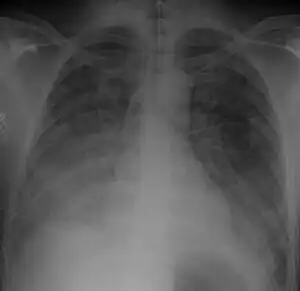

Chest Xray of a 40 yr old male in acute respiratory distress syndrome as a complication of murine typhus